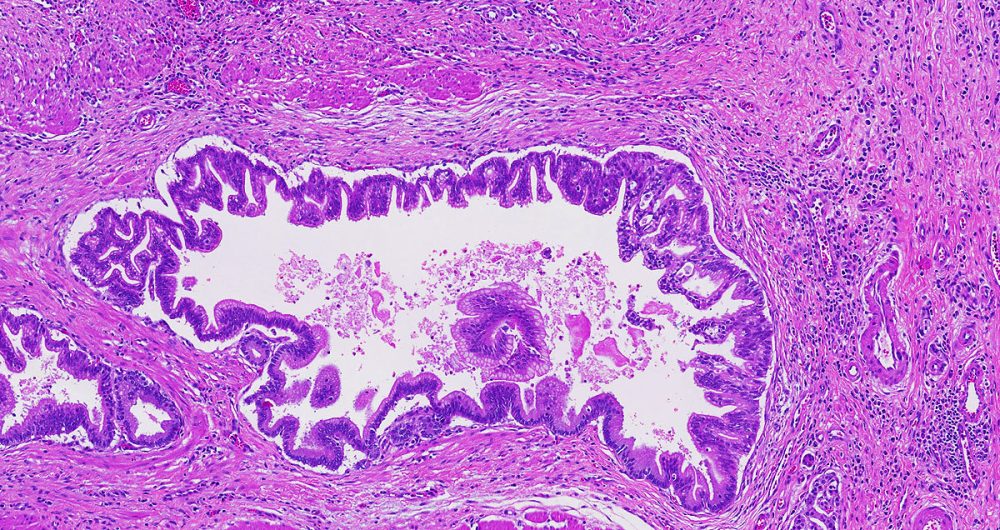

High-grade pancreatic intraepithelial neoplasia replaces the older term- PanIN-3.